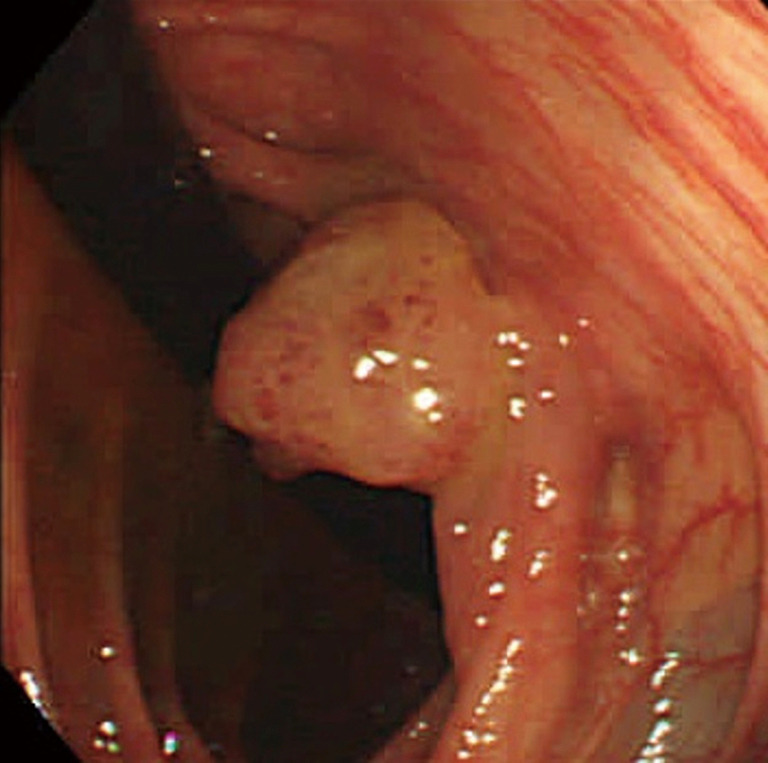

This paper presents case studies of adult patients with congenital heart disease (CHD) who developed cancer and also discusses relevant epidemiological studies, risk factors, and reports on early detection. Herein, we describe three cases: a 63-year-old man with an atrial septal defect and multiple myeloma; a 48-year-old man with tetralogy of Fallot and colorectal cancer; and a 25-year-old man with Fontan circulation and hepatocellular carcinoma (HCC). Previous studies have found that the incidence of cancer in adult patients with CHD is higher than that in the general population. The management of adult patients with CHD complicated by cancer requires careful attention because cancer treatment alone can affect the survival prognosis and quality of life, as well as the pathophysiology and treatment of underlying heart disease. Apart from known risk factors in the non-CHD population, specific risk factors have been reported, such as genetic abnormalities, low-dose ionizing radiation exposure, early thymectomy, Fontan-associated liver disease, and hypoxia. Encouraging patients to participate in cancer screening and avoid known risk factors is essential in daily practice for the early diagnosis and prevention of cancer. It is also important to be vigilant for initial signs that are indicative of cancer as well as avoidable risk factors.

Abstract Image